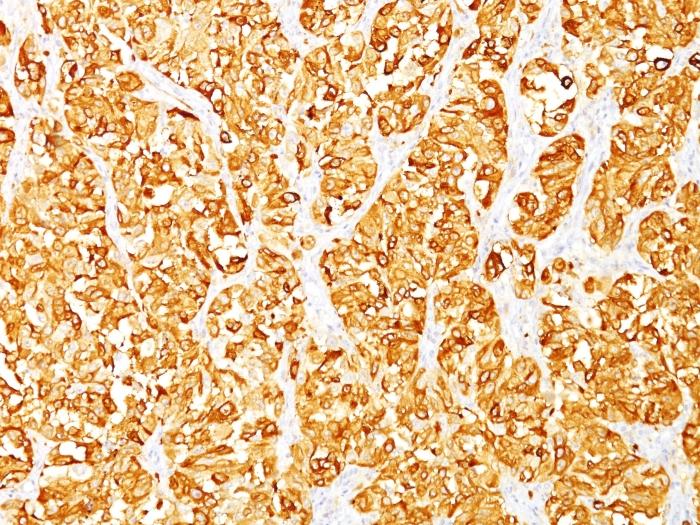

This antibody recognizes a protein doublet of 20-22 kDa, identified as MART-1 (Melanoma Antigen Recognized by T cells 1) or Melan-A. MART-1 is a newly identified melanocyte differentiation antigen recognized by autologous cytotoxic T lymphocytes. Seven other melanoma associated antigens recognized by autologous cytotoxic T cells include MAGE-1, MAGE-3, tyrosinase, gp100, gp75, BAGE-1, and GAGE-1. Subcellular fractionation shows that MART-1 is present in melanosomes and endoplasmic reticulum. This MAb labels melanomas and other tumors showing melanocytic differentiation. It is also a useful positive-marker for angiomyolipomas. It does not stain tumor cells of epithelial, lymphoid, glial, or mesenchymal origin. Primary antibodies are available purified, or with a selection of fluorescent CF® Dyes and other labels. CF® Dyes offer exceptional brightness and photostability. Note: Conjugates of blue fluorescent dyes like CF®405S and CF®405M are not recommended for detecting low abundance targets, because blue dyes have lower fluorescence and can give higher non-specific background than other dye colors.

Positive Control

SK-MEL-13 and SK-MEL-19 melanoma cell lines. Human melanoma tissues.

Tumor expression

Melanoma

Antibody applications

IHC, FFPE (verified)

IHC (FFPE) (verified)